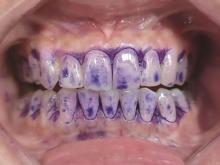

郭曼丽, 张植栋, 包广洁. 探讨以菌斑控制为导向治疗牙周病的思考[J]. 中国医药指南, 2022, 20(31): 72-75.

Guo ML, Zhang ZD, Bao GJ. Plaque control-oriented periodontal therapy[J]. Guide China Med, 2022, 20(31): 72-75.